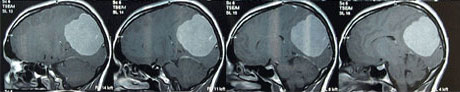

Eine MRT -Untersuchung (Computertomographie) des Schädels wurde sofort organisiert.

Befund: linksseitiger, occipitaler, ca. 45 x 60 mm großer Tumor

MRT-Bilder präoperativ (vor der Operation):